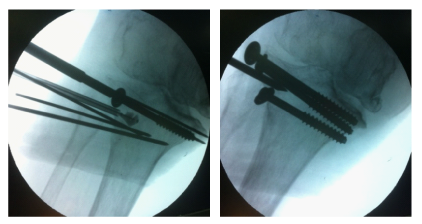

The contrast medium allowed for continuous monitoring of the reduction process under fluoroscopy in multiple views. When adequate reduction was achieved, two more K-wires were placed just above the inflated balloon to support the reduction and prevent any secondary loss of correction. The balloon was then deflated and withdrawn and two cannulated screws with washers were placed over the K-wires through small stub incisions. One more cannulated screw with a washer was placed below the balloon position and the K-wires were also withdrawn (Figure 4). We then injected calcium phosphate cement through the trocar, filling the balloon-created cavity of the lateral tibial plateau and augmenting the fracture. The volume of the cement was determined by the volume of the contrast solution used with the balloon and the injection was carefully done under fluoroscopy, to avoid excessive cement overflow into the tibial medullary cavity (Figure 5). The final reduction and osteosynthesis were radiologically verified and the stub incisions were closed. The knee effusion was aspirated - giving roughly 200 cc of blood - and a compressive bandage was applied.

Figure 4 Fracture supporting K-wires, balloon deflation, and screw fixation.